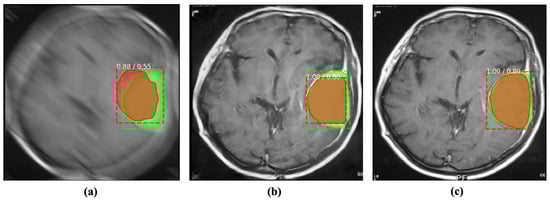

Abnormality segmentation is considered among the most prominent CAD applications in medical image analysis. Despite having substantial real-world implications, medical image segmentation suffers from blind-motion blur. As Figure 6 illustrates, the existing segmentation methods’ performance can drastically deteriorate by blind-motion blur. A robust deblurring method can help segmentation methods in improving their performance. Here, we evaluated the SOTA U-net architecture inspecting the impact of blurs in segmentation on MRI images.

Figure 6. Incorporating the proposed method for deblurring medical images can improve medical image segmentation performance. The red and green regions represent the area segmented by the deep model and the actual (ground-truth) affected region. (a) Blurry image + U-Net [36]. (b) Deblurred image obtained by proposed method + U-Net [36]. (c) Reference image + U-Net [36].